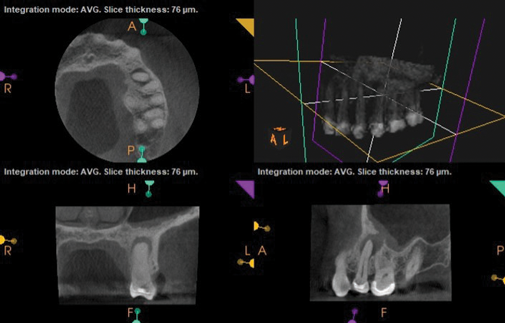

Fig 7 and Fig 8. Preoperative CBCT scans showing evidence of periapical pathology on tooth No. 14 as well as communication with the adjacent maxillary sinus and associated mucositis. Fig 7: Sagittal view, buccal roots No. 14. Fig 8: Sagittal view, palatal root No. 14.

Figure 7

Fig 8. Preoperative CBCT scans showing evidence of periapical pathology on tooth No. 14 as well as communication with the adjacent maxillary sinus and associated mucositis. Fig 7: Sagittal view, buccal roots No. 14. Fig 8: Sagittal view, palatal root No. 14.

Figure 8

As part of the endodontic evaluation, CBCT imaging showed periapical pathology associated with tooth No. 14 as well as significant MSEO (Figure 7 and Figure 8). Clinical testing confirmed the absence of a cold response but no tenderness to percussion or palpation. A composite buildup was in place, absent evidence of recurrent decay. Soft tissues were unremarkable.

The diagnosis for tooth No. 14 was pulpal necrosis with asymptomatic apical periodontitis. NSRCT was completed (Figure 9), followed by full-coverage restorative care performed by the general dentist. A 3-month follow-up revealed resolution of prior sinus symptoms, normal clinical findings, and healing radiographic pathology, including periapical pathology and associated maxillary sinus mucositis (Figure 10 and Figure 11).

Both of these cases illustrate the improvement in sinus pathology findings from preoperative CBCT scans to postoperative recall CBCT scans following NSRCT (Figure 4, Figure 10, and Figure 11). In addition, in both instances the re-establishment of the previously obliterated cortical boundary between the apex and maxillary sinus was impressive. Clinically, the resolution of sinusitis symptoms in both patients after receiving nonsurgical endodontic therapy was quite notable. Despite the absence of specific dental pain, these patients' sinusitis symptoms could not have been alleviated without the endodontic interventions due to the odontogenic etiology of their disease. These two cases demonstrate the pivotal role of CBCT imaging in diagnosis and recall as well as the success of NSRCT when treating cases of MSEO.